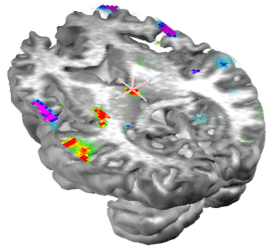

To localize the generators of the sleep spindles we used the simplified SYSMAC head model and the variant of ELECTRA source model based on the estimation of intracranial potentials. The SYSMAC model was constructed on the basis of a standard head model since the subject individual MRI was not available. A total of 4024 knots, homogeneously distributed over the gray matter, composed the solution space for an effective resolution of 6 millimeters. Conductivities for the lead field construction were assumed as in Stok.

The localization results for the spindles at 12 and 14 Hz shown in Figure 6 are displayed in Figure 7 and 8 respectively. While the localization results cover the same period than in Figure 6, we have reduced the number of images shown over the interval to facilitate visualization of the results. The localization results are very stable over the spindle period as expectable from the stability observed for the scalp maps. The slower spindles at 12 Hz have maximum (minimum) that localize to the middle frontal lobe (Brodmann area 9). The frontal localization was consistently observed over several explored spindles although some spindles showed maxima at the inferior frontal gyrus rather than the middle frontal gyrus shown here. Hemispheric lateralization was not clear though most spindles start at the left or right hemisphere and progress towards a more bilateral involvement around the spindle peak.

Magnify

Figure 7. ELECTRA localization for the slower spindles at 12 Hz. The sequence of maps represents the temporal evolution of localization over the spindle cycle. Maxima (positive potential) are represented in red an marked with a red cross and minima in blue with a blue cross indicating the exact position. Note that the maxima and minima remain stable over the window except for the poalrity inversions.

The maxima for faster spindles at 14 Hz were systematically localized at parietal or parieto-occipital areas as shown in Figure 8. Curiously, the frontal spindles progressively involved anterior cingulate areas toward the spindle maximum while parietal spindles recruited motor cortical areas during their development. Apparently, the increase in amplitude of the spindles is not only due to the increase in activity at frontal or parietal areas but also to the progressive recruitment of additional structures anatomically connected to the site where the spindle initially developed, i.e., frontal cortex to cingulate and parietal cortex to motor areas.

Figure 8. ELECTRA localization for the faster spindles at 14 Hz. Note that the maxima and minima remain stable at parietal locations over the spindle cycle except for the polarity inversions. Note the progressive recruitment of sensory-motor cortex over the cycle.